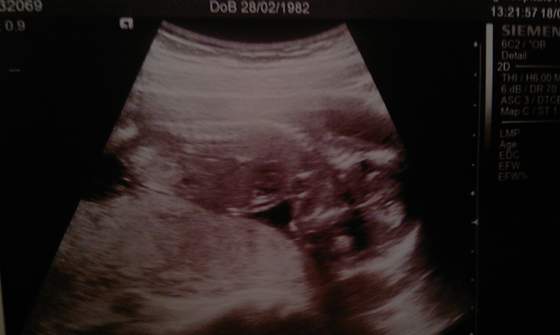

a o to dzisiejsze zdjecie, dzidzia jest do gory nogami jakos, hmm..

baby 16t6d.jpg